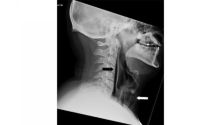

Bersin Terlalu Keras, Pria Ini Malah Kena Stroke

Akibat Tahan Bersin, Tenggorokan Pria Ini Akhirnya Pecah